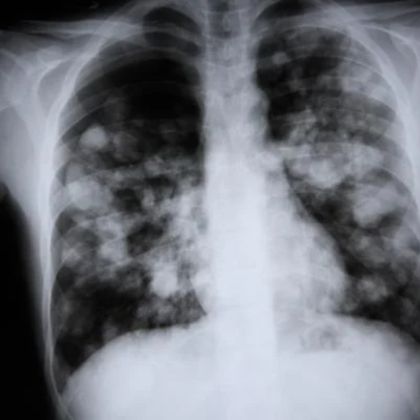

- Zapalenie płuc: Odra może prowadzić do powikłań związanych z układem oddechowym, takich jak zapalenie płuc, które może być poważne, zwłaszcza u osób starszych lub osób z obniżoną odpornością.

Odra może również powodować powikłania układu oddechowego, takie jak zapalenie płuc i zapalenie oskrzeli. Te infekcje mogą być poważne, szczególnie u osób z osłabionym układem odpornościowym. W niektórych przypadkach mogą one prowadzić do hospitalizacji i wymagają specjalistycznego leczenia.